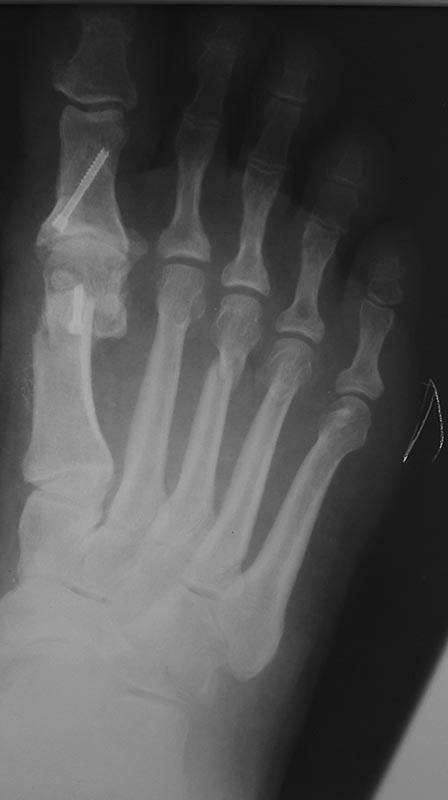

По просьбам трудящихся)) сегодня сделан шеврон Эйкин 3dmmo!)) остеотомия вышла стабильно! Накосячил с параболой , не дал достаточного укорочения m1! Нужен опыт!))